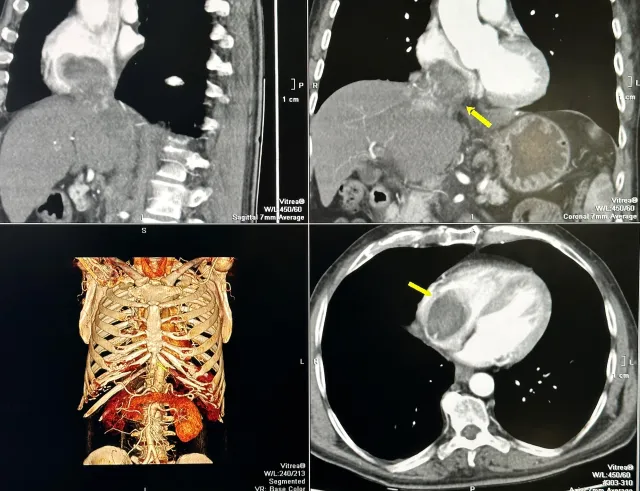

Туморът с размери е заел и извършил съвсем напълно кухината на дясното предсърдие на сърцето и е застрашавал да запуши белодробните артерии и белия дроб.

Туморът се популяризира и като обгръща и запушва прехода на долна празна вена, преминаваща през черния дроб. Размерът на туморното образувание в този сектор е с дължина 17 сантиметра и ширина три сантиметра.

Екип на Клиниката по кардиохирургия на УМБАЛ „ Проф. доктор Александър Чирков “ под управлението на проф. Димитър Петков отстранява изцяло туморите от сърцето и от цялата долна празна вена, намираща се в чернодробния сектор.